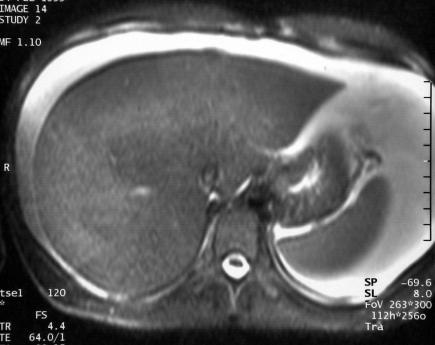

L'IRM est demandée pour faire le bilan.

T2